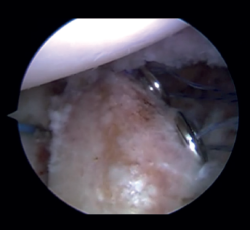

Figure 3. View from the anterosuperior portal (left shoulder). Monofilaments inserted through the sheaths from posterior to anterior for subsequent passing of the threads that will introduce the graft.

Arthroscope is introduced through the anterosuperior portal, and the glenoid guide is introduced through the posterior portal, and passed paralel to the glenoid surface until the hook is located at the centre of the bone defect. The guide is secured with two cannulas inserted through two small accessory incisions, until connecting with the posterior cortical layer. Both cortical layers are drilled through them using a 2.8 mm drill fitted with a sheath so that on withdrawing the drill the sheath is positioned at drilling level. This step is made twice to introduce two sheaths: one above and the other below the glenoid guide hook and spaced 10 mm apart. Through these sheaths we advance two monofilament loops that are retrieved sequentially through the anterior portal for subsequent passing of the graft. At this point we can remove both sheaths and the glenoid guide, taking care to prevent the guide hook from coming into contact with the glenoid surface in order to avoid damaging to the cartilage.